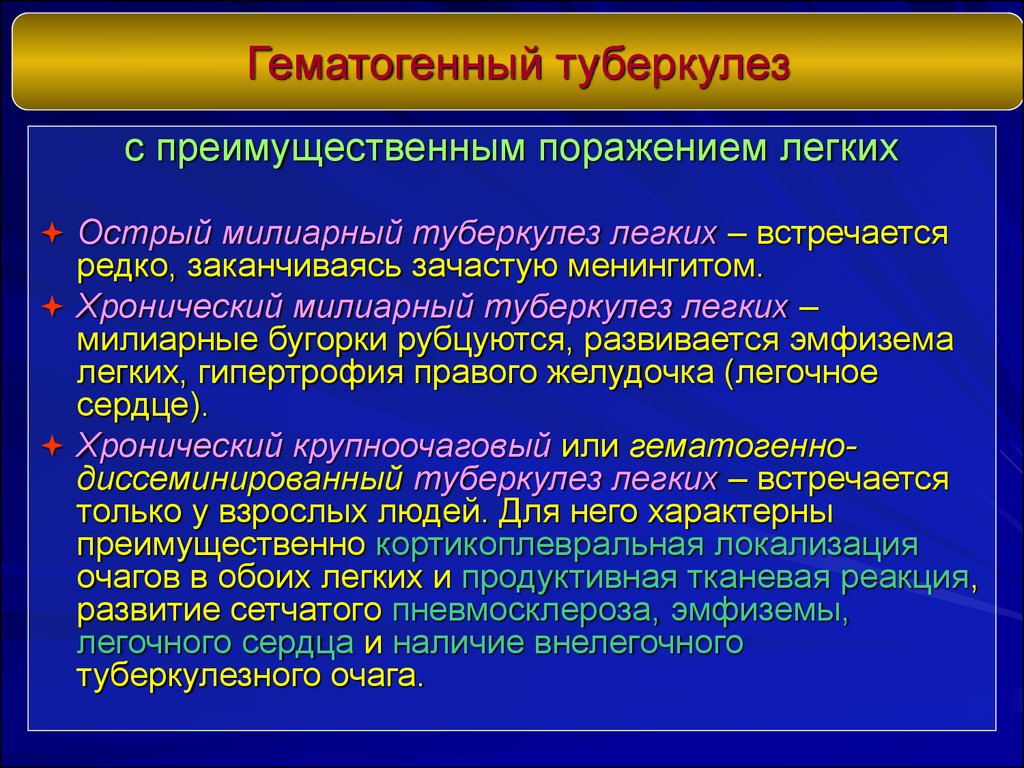

В клинической картине острого гематогенно диссеминированного туберкулеза преобладает